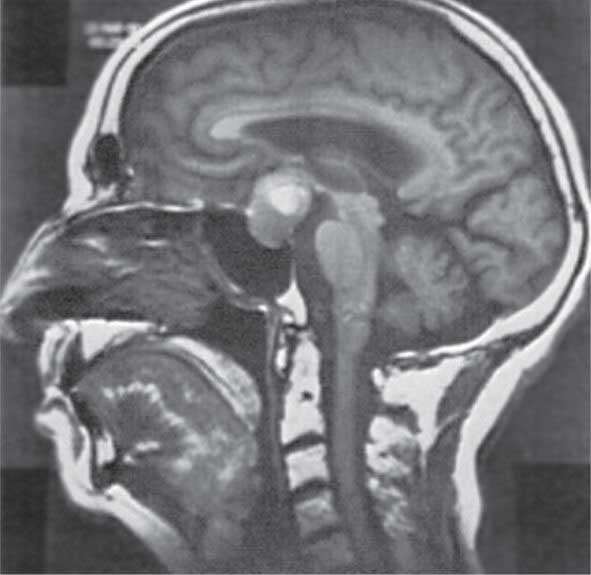

الاستقصاءات الشعاعية للنخامى: يعد المرنان (MRI) حالياً الوسيلة الشعاعية المثلى لكشف الآفات النخامية. ولكن ما يزال التصوير المقطعي المحوسب (CT) مفيداً في إظهار التكلسات في الأورام (مثال الورم القحفي البلعومي)، أو إظهار التخرب العظمي في البنى العظمية المحيطية.

![]() | ![]() |

ورم نخامي عرطل ممتد من الأعلى ضاغطاً التصالب البصري | ورم نخامي عرطل يضغط البنى المحيطة بالنخامة |